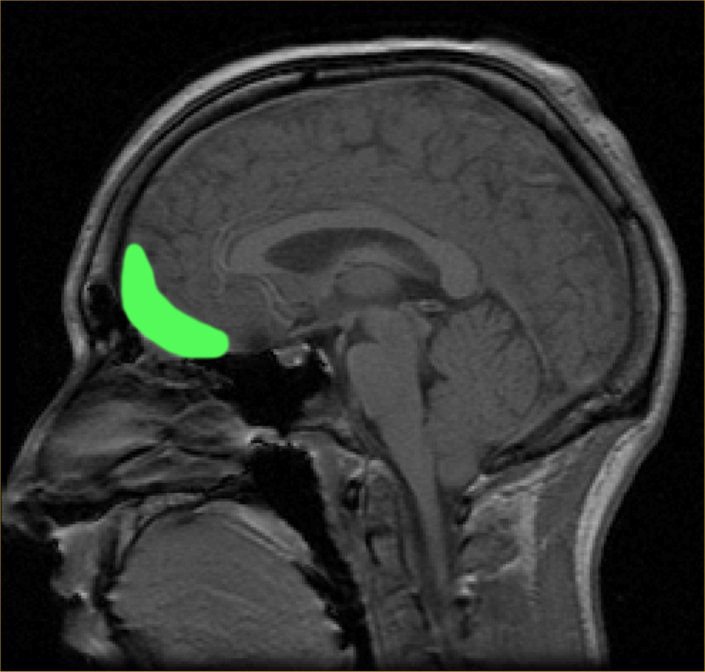

Отже, коли ви міркуєте, з’їсти на десерт морозиво чи шоколадний торт – за вибір найкращого варіанту для вас відповідає орбітофронтальна кора мозку, розташована прямо над нашими очима.

Пацієнти з пошкодженням цієї ділянки мозку не тільки роблять неправильний вибір – вони ще й використовують несумісну інформацію, коли між чимось вагаються.

Потім дослідники помістили крихітні електроди в орбітофронтальну кору кожної мавпи. Електроди безболісно стимулювали нейрони, що представляють цінність кожного варіанту. Кожна мавпа вказала на свій вибір, лише кинувши на неї погляд.